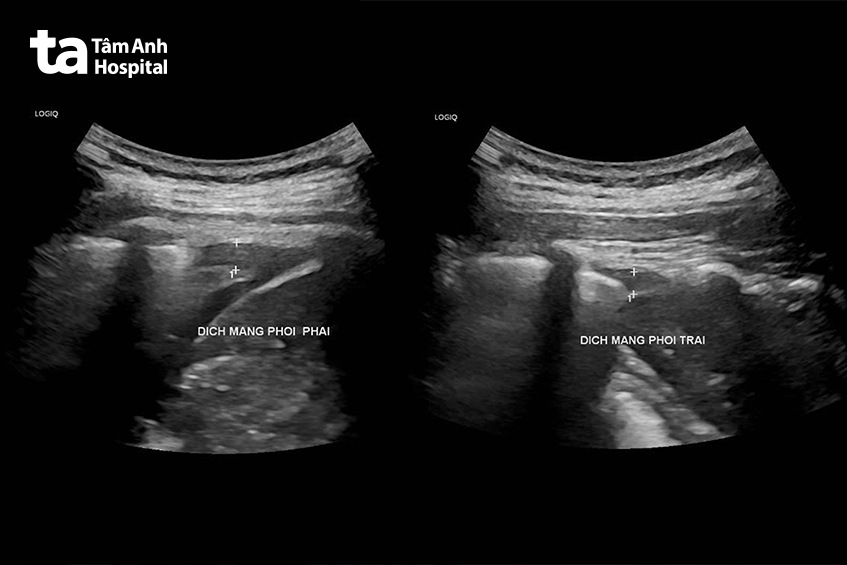

Do người bệnh đang mang thai 22 tuần không thể chụp cắt lớp vi tính, X-quang ngực, bác sĩ chỉ định cho chị Hạnh siêu âm phổi, màng phổi. Đây là biện pháp cận lâm sàng đóng vai trò quan trọng trong chẩn đoán viêm phổi ở phụ nữ mang thai nhằm tránh phơi nhiễm tia X. Kết quả cho thấy người bệnh có tổn thương phổi lan rộng kèm theo tình trạng tràn dịch màng phổi cả hai bên.

Cụ thể, phần dưới của phổi trái, gần sát thành ngực phía sau, có một vùng mô phổi bị đông đặc (kích thước khoảng 20x10x7,5mm). Tương tự, phần dưới của phổi phải, gần sát thành ngực phía sau, có một vùng đông đặc lớn hơn (kích thước 24,9×15,4mm).